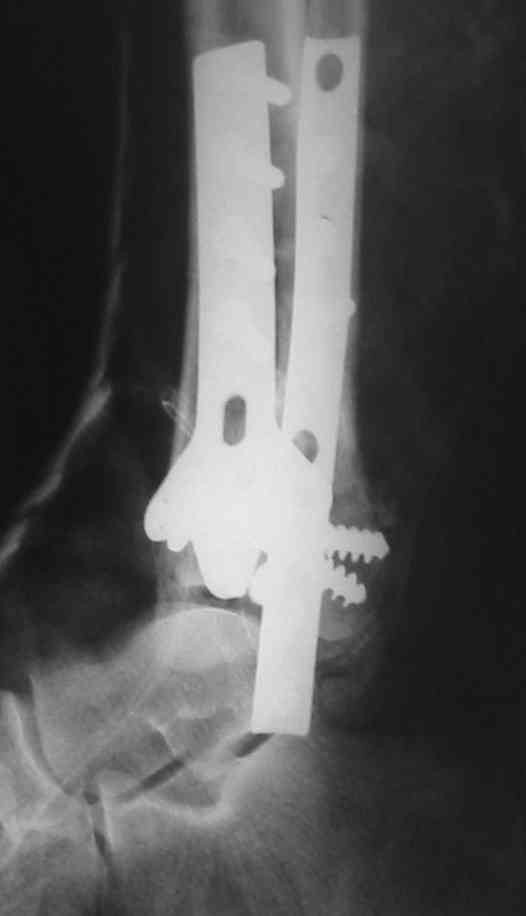

OK, Dr Driagin, Ja operiroval bolnogo po Vashemu, hotia sam ni ochen' ubezden' v itom, t.k. bolnoi otkazalsa na proch' ot ex.fix, ja emu sdelal ORIF + Kostnia plastika, snimky prelogiottsa,

Очень прилично получилось, но мне показалось, что винты на 4,5 мм.Это принципиально винты используются 3,5 и 4,0 мм. И проекцию прямую бы переделать. С уважением Дрягин

На представленном снимке видно, что эпифиз смещен латерально.

Сейчас с этим ничего не сделать, похоже.

Однозначно сказать сложно.Расстояние между тараном и медиальной лодыжкой меньше чем между тараном и крышей большеберцовой кости.Это может быть за счёт не правильной укладки.Пока не отчаиваетесь.Главное вы поняли принцип.Сделайте несколько проекций прямых и посмотрим.Для всех интересно.С уважением

Мне кажется, что все конечно далеко от идеала. Сложный перелом. Есть ощущение, что малоберцовая кость (ключ!) фиксирована с ротацией и удлинением. Снимки конечно необходимо сделать в правильных проекциях и без гипса...

В голеностопном суставе обязательны 3 стандартные ренгенологические проекции: прямая, латеральная и мортиз. Без них невозможно трактовать состояние голеностопа.